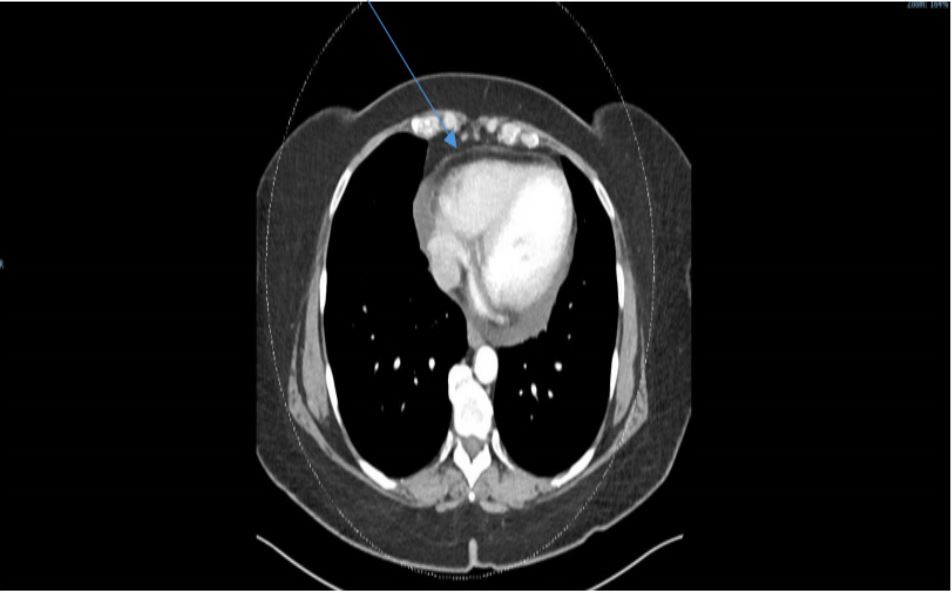

An ultrasound of the abdomen was performed in view of the elevation of the serum transaminases. The liver appeared normal but there was a suspicion of a pancreatic cyst. An abdominal CT scan did not show a pancreatic cyst but did detect a pericardial effusion. She therefore was referred for a transthoracic echocardiogram that revealed new-onset heart failure with hypokinesia in the inferior and septal walls and an ejection fraction of 45%, in addition to a moderate pericardial effusion. Coronary angiography revealed normal coronary arteries. The patient was discharged home on standard therapy consisting of bisoprolol, aspirin, atorvastatin and dapaglifozin.

Figure 1: CT scan of the chest revealing a pericardial effusion (arrow)

We present a case of a 56-year-old woman who was admitted for investigation of weakness and abdominal pain. She was usually healthy with no regular medication. Two weeks prior to her admission she developed severe vomiting and acute renal failure with a serum creatinine of 4.1 mg/dL. This resolved following supportive treatment with iv fluids. A review of her laboratory tests showed an elevation in her serum transaminases together with an increase in CKMB and a subsequent increase in LDH (Table 1). Abdominal imaging by ultrasound and CT scan was normal but did detect a pericardial effusion 1. At this stage transthoracic echocardiogram was carried out (Figure 2), which detected inferior and apical hypokinesia together with an ejection fraction that was reduced to 45% and a pericardial effusion. Coronary angiography revealed normal coronary arteries.